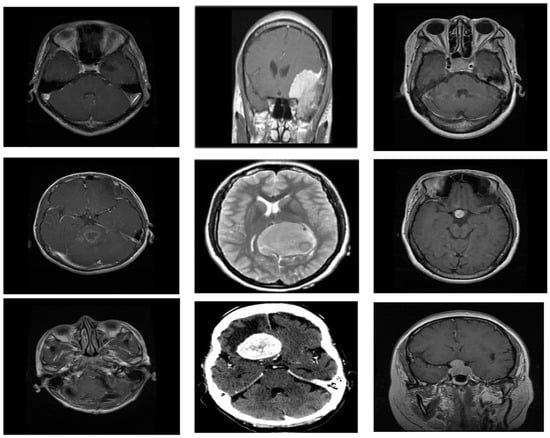

3. Materials and Methods

- (a)

- Glioma:

- (b)

- Meningioma:

- (c)

- Pituitary: